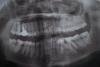

neth Опубликовано 18 августа, 2012 Автор Поделиться Опубликовано 18 августа, 2012 (изменено) заберу в поликлинике в понедельник обязательно выложуесть только панорама но она пораньше сделанасегодняшней ночью боли не было совсем. значит ли что нерв умер за 2 дня или нет? может обошлось без пульпита?очень не хотелось бы удалять нерв. последнее время было нервное состояние что горло сдавливало. может просто как говорят все болезни от нервов?37 зуб Изменено 18 августа, 2012 пользователем neth Ссылка на комментарий

ger_berra Опубликовано 19 августа, 2012 Поделиться Опубликовано 19 августа, 2012 (изменено) остался кариес на 37 под пломбой ближе к десне,поэтому в этом месте она воспаляется.Надо пломбу снять и почистить.Пульпита в нём нет(судя по снимку).И к ортодонту.С прикусом совсем беда((26 -кариес под пломбой. Изменено 19 августа, 2012 пользователем ger_berra Ссылка на комментарий

neth Опубликовано 21 августа, 2012 Автор Поделиться Опубликовано 21 августа, 2012 снимок 4хдневной давности Ссылка на комментарий

ger_berra Опубликовано 22 августа, 2012 Поделиться Опубликовано 22 августа, 2012 (изменено) ОРТОДОНТ исправляет прикус,а не ОРТОПЕД. Удалить придётся зубы мудрости и скорее всего лежачий 35.Нервы из всех зубов удалять не надо!Что Вы?Бог с Вами! Прицельный снимок плохой.Ничего не понятно. Изменено 22 августа, 2012 пользователем ger_berra Ссылка на комментарий